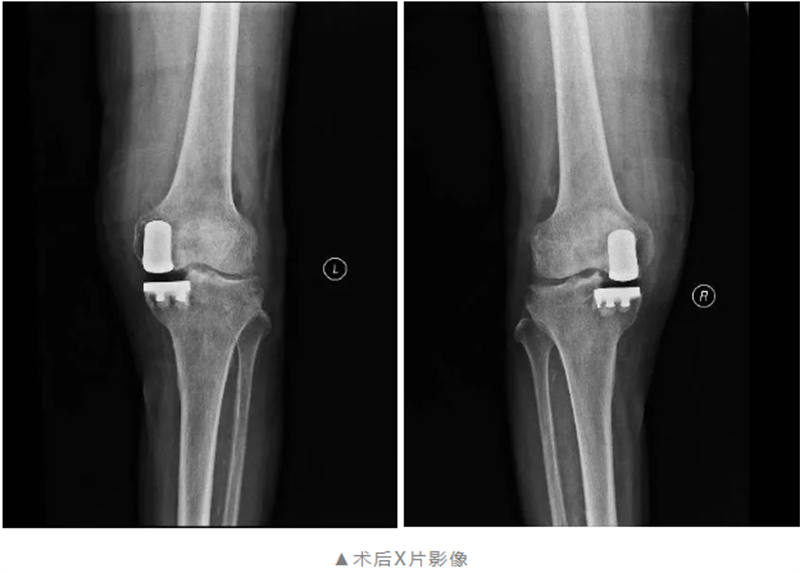

經(jīng)過(guò)術(shù)前的精心準(zhǔn)備,術(shù)中麻醉科團(tuán)隊(duì)的大力支持,關(guān)節(jié)骨病科團(tuán)隊(duì)僅用不到2個(gè)小時(shí)就順利完成了雙側(cè)膝關(guān)節(jié)單髁置換術(shù)。術(shù)后在關(guān)節(jié)骨病科醫(yī)護(hù)團(tuán)隊(duì)的精心護(hù)理與康復(fù)指導(dǎo)下,黃阿公雙膝關(guān)節(jié)痛感明顯減輕,膝關(guān)節(jié)功能逐步恢復(fù),已能自主下床活動(dòng),被疾病折磨30余年終于重獲新生。

經(jīng)過(guò)全面細(xì)致的檢查與多學(xué)科會(huì)診評(píng)估,關(guān)節(jié)骨病科團(tuán)隊(duì)在與黃阿公及其家屬充分溝通后,制定了個(gè)性化的膝關(guān)節(jié)手術(shù)方案——雙側(cè)膝關(guān)節(jié)單髁置換術(shù),在膝關(guān)節(jié)磨損的部位植入特殊材料的“墊片”,最大限度的保留了患者的本體感覺(jué)和關(guān)節(jié)功能。